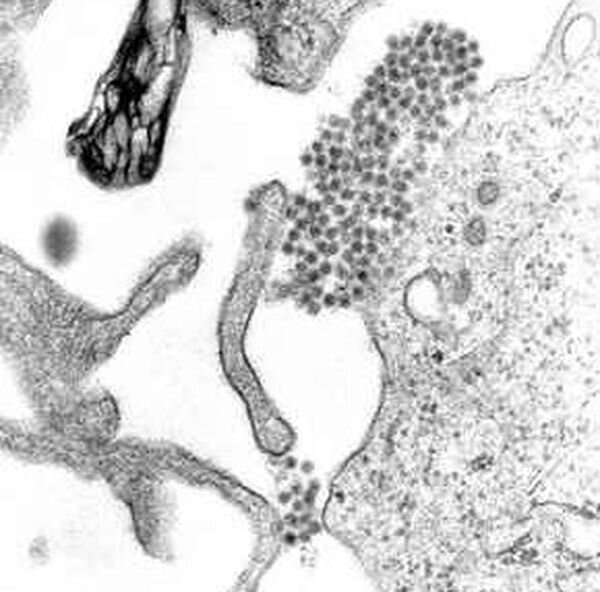

Исследователи из Южного федерального университета совместно с учеными из Китая и Словении изучили способ, с помощью которого некоторые из вирусов собираются из белковых молекул в клетках. Потенциально исследование может помочь создать препараты для лечения и профилактики некоторых вариантов лихорадки. Итоги исследования опубликовал научный журнал Nanoscale Advances.

Ученые сосредоточились на том, каким образом молекулы в пораженных вирусом клетках собираются в оболочку вируса. Оболочки вирусов, если попытаться их представить, похожи на футуристические жилища из ячеек правильной формы. И до сих не была изучена ситуация, когда оболочки вирусов собираются из одинаковых ячеек с количеством молекул меньше пяти. Так ведет себя, например, вызывающий лихорадку вирус Денге.

Специалисты создали математическую модель и проверили ее на компьютерах. Модель показала, что молекулы ячеек оболочки вирусов выстраиваются так, чтобы центры тяжести молекул соответствовали определенному правилу.

Однако более важным ученые считают открытие правил, по которым «молодые» вирусы перестраивают свои оболочки внутри клетки перед выходом наружу. Зная это правило, можно создать препараты, нарушающие этот процесс. А значит замедляющие распространение вируса в организме.